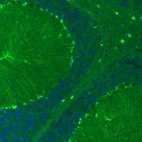

Immunohistochemistry analysis in human cerebral cortex and kidney tissues using AMAb91038 antibody. Corresponding S100B RNA-seq data are presented for the same tissues.